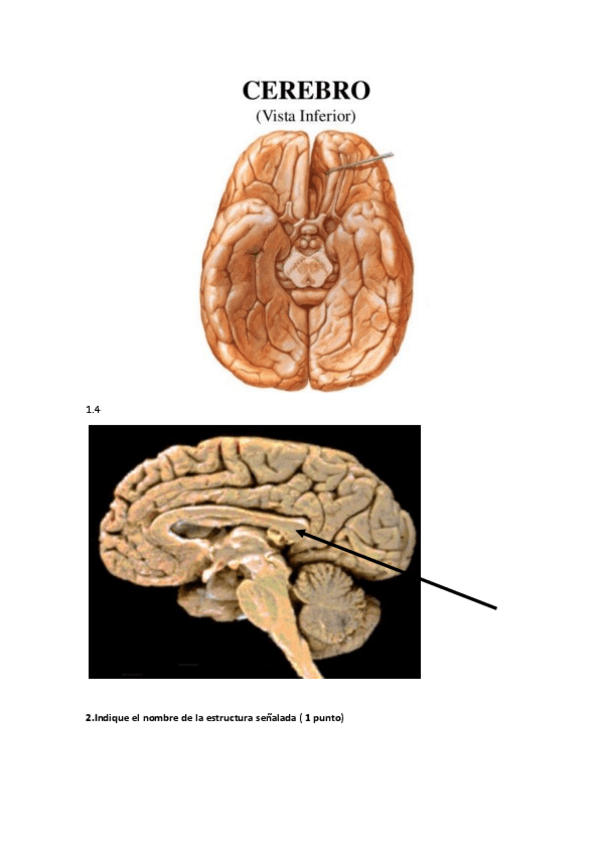

Este es el modelo C del examen de neuro de 2022 2023, había 6 modelos distintos